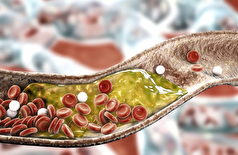

- آلودگی هوا بیسروصدا قلب را تهدید میکند!

- یک دوز از داروی جدید میتواند کلسترول را برای تمام عمر کاهش دهد

- میوهای که کلسترول خون را کاهش میدهد